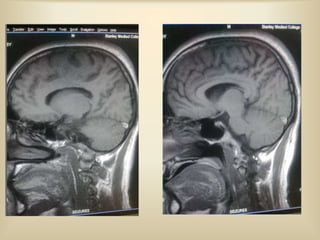

MRI FINDINGS IN CVT

 Can confirmatively tell presence of CVT.

 Venous thrombus may be directly visualised.

 Patent dural sinuses are seen as flow void

especially when the image is orthogonal to blood

flow direction.

 Thrombus manifest as absence of flow void-best

seen in FLAIR and T2 weighted spin echo

sequences.

 T1 weighted - hyperintensity ; T2 weighted

gradient echo-exaggerated signal loss.

 MR venography - shows direct visualisation of

thrombus.